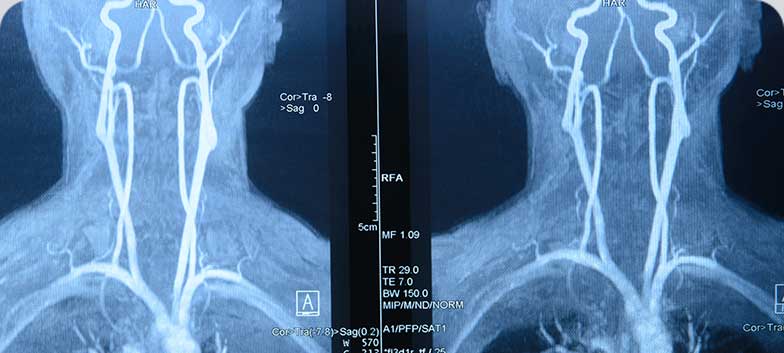

Carotid artery stenosis

Refers to the narrowing of these arteries, which may compromise cerebral blood flow and lead to ischemic events.

• CT scan or cranioencephalic magnetic resonance imaging (MRI-CE)

• Carotid Doppler